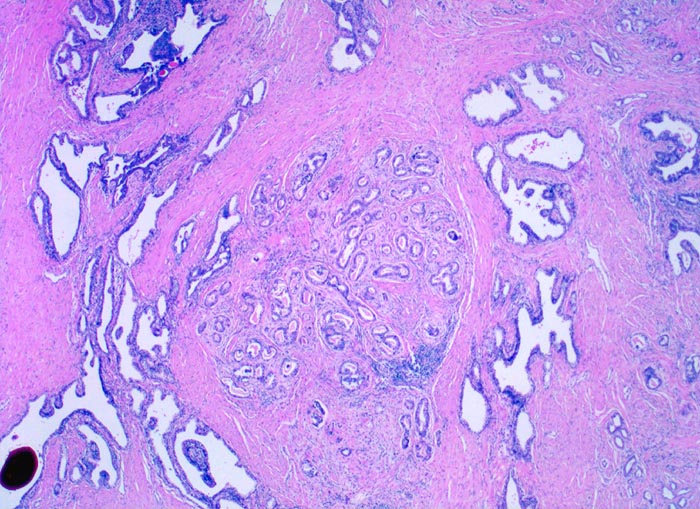

• Herde kleiner Karzinomdrüsen ohne Basalzellschicht.

• Fehlende lobuläre Anordnung der Karzinomdrüsen.

• Wenig differenzierte Karzinomanteile ohne erkennbare Drüsenbildung.

• Perineuralscheideninvasion.

• Unterhalb der Samenblase sind von flachem Endothel ausgekleidete Lymphgefässe mit Karzinominfiltraten erkennbar (Lymphangiosis carcinomatosa).